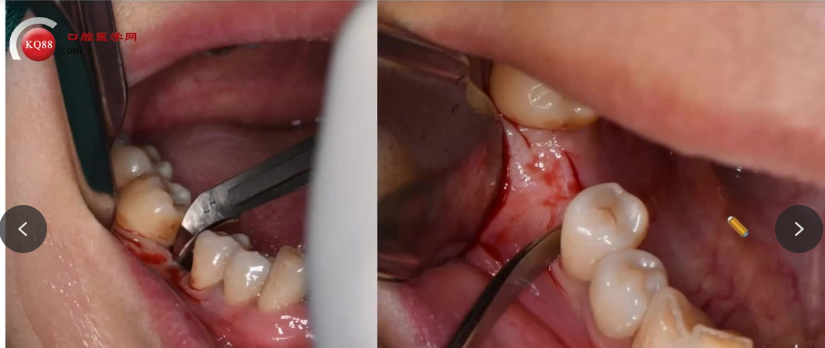

手术操作:麻醉后切开、翻瓣,逐级扩孔(注意提拉与冷却),植入种植体。

愈合方式选择:根据骨质与稳定性,放置覆盖螺丝或愈合基台,缝合创口。